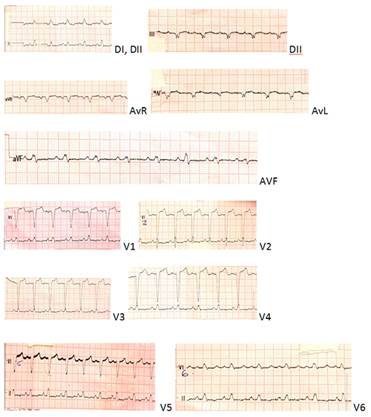

Se realiza electrocardiograma (Figura 2), troponinas cardiacas de valor intermedias y ecocardiograma (ETT) que evidencia hipertrofia excéntrica del ventrículo izquierdo, alteraciones sectoriales, aquinesia septal e inferior en todos sus sectores, con una fracción de eyección del ventrículo izquierdo (FEVI) de 30%. Aurícula izquierda moderada a severamente dilatada, insuficiencia aórtica y mitral leve. Función del ventrículo derecho conservada.

Figura 2: Electrocardiograma 12 derivaciones. Taquicardia sinusal y bloqueo completo de rama izquierda (BCRI) ya presente en electros previos

Se realiza diagnóstico retrospectivo de Miocarditis por H1N1 con presentación de miocarditis fulminante. No contamos con resonancia nuclear magnética (RNM) debido a que el diagnóstico se realizó de forma retrospectivo. Pero apoyan el diagnóstico las alteraciones electrocardiográficas sugestivas, troponinas cardiacas positivas, caída de la función ventricular con posterior recuperación y aislamiento microbiológico de agente causal.